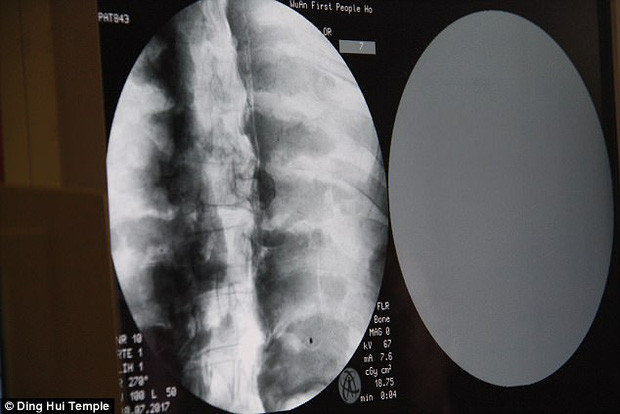

Cụ thể, các chuyên gia tiến hành chụp X-quang xác ướp nhà sư Từ Hiền. Nhờ vậy, họ phát hiện thi hài nhà sư Từ Hiền vẫn còn đầy đủ xương cũng như sọ não.

Theo các chuyên gia, xương hàm trên, hàm dưới, xương sườn, cột sống và tất cả khớp của nhà sư Từ Hiền đều hoàn chỉnh. Điều này khiến giới khoa học cảm thấy bất ngờ và khó tin.